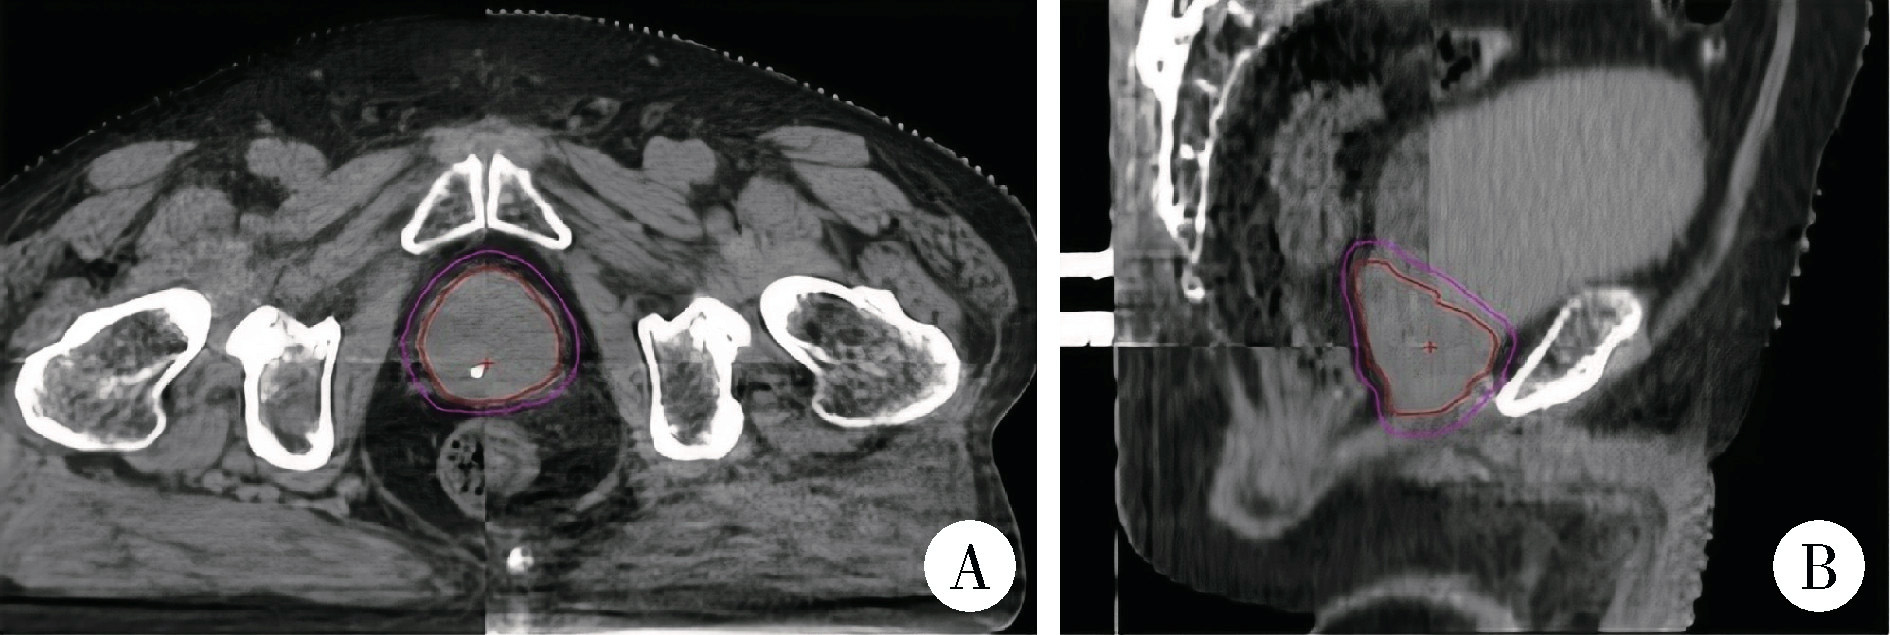

两组患者均采用常规CT扫描进行定位,扫描参数为管电压120 kV、层厚3 mm。采集到的图像传输至MIM Maestro 7.1.6(MIM)软件, 与患者既往的磁共振(magnetic resonance imaging,MRI)图像进行融合。医生在融合图像上进行靶区勾画,PTV为CTV向各个方向外扩5 mm,其中直肠前壁区域的PTV被适当收回以减少正常组织受量(图 2显示了前列腺根治性放射治疗患者的CBCT图像,其中红色线表示CTV,橙色线表示PTV,直肠侧的PTV已收回,图 2A图 2B分别为CT的轴位图像和矢状位图像,图 2C图 2D为MRI的轴位和矢状位图像)。所有患者的定位图像传输至Monaco治疗计划系统,由物理师完成计划设计并进行验证。

图2 前列腺癌放射治疗患者的定位CT与MRI图像及靶区

Figure 2 Localization computed tomography (CT) and magnetic resonance imaging (MRI) images and target volumes of a patient treated with definitive radiotherapy for prostate cancer

A, axial CT images; B, sagittal CT images; C, axial MRI T2WI sequence images; D, sagittal MRI T2WI sequence images.